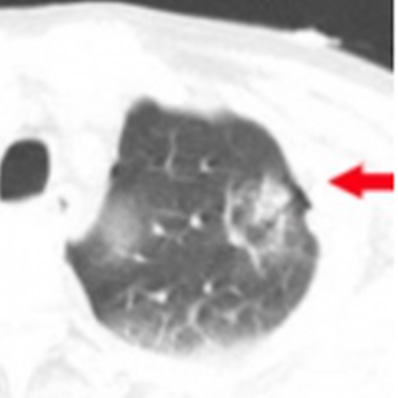

外傷性気胸

肺挫傷

外傷性血胸